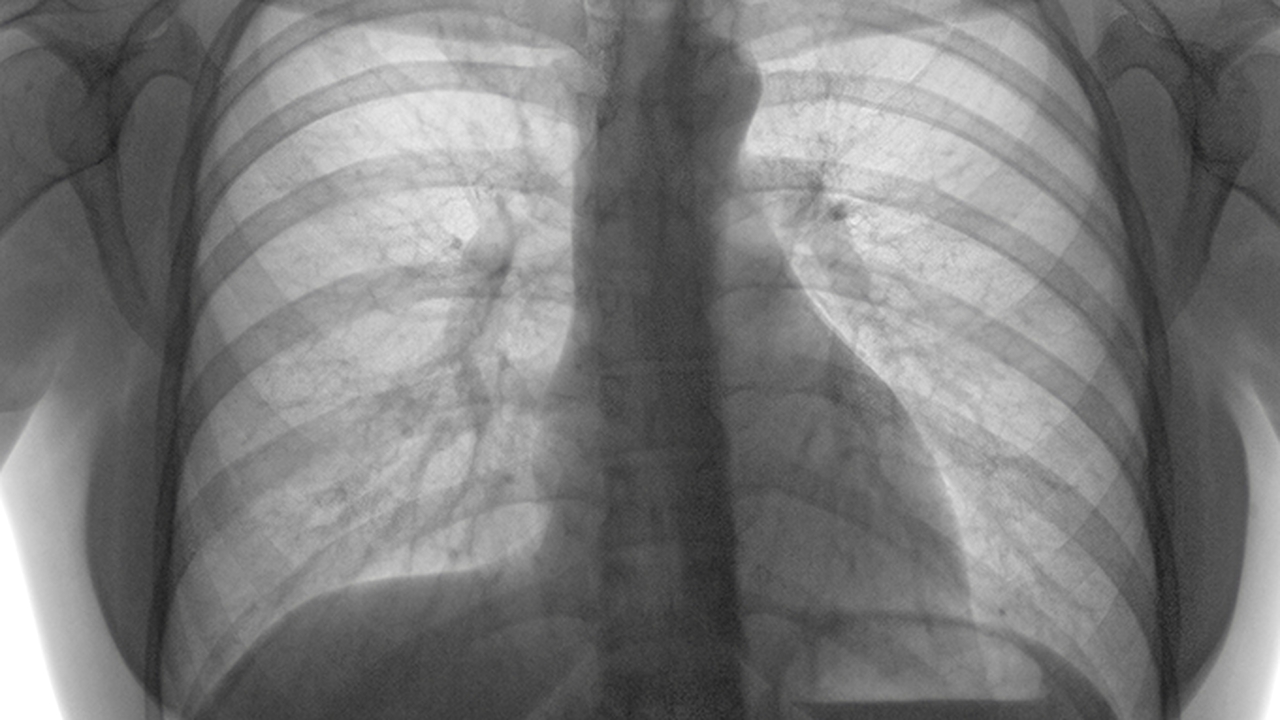

肺癌的发病原因复杂多样,长期吸烟、空气污染、职业暴露、遗传因素等都可能增加患病风险。早期诊断和规范治疗对提高生存率至关重要。

肺癌预防与健康管理至关重要。建议40岁以上人群,特别是长期吸烟者、有家族史者、职业暴露人群等高风险人群定期进行低剂量螺旋CT筛查。日常生活中应戒烟限酒,避免接触二手烟和空气污染,保持健康饮食和适度运动。出现持续性咳嗽、痰中带血、胸痛等症状时应及时就医。确诊肺癌后,应选择正规医疗机构接受规范治疗,同时保持良好的心态和健康的生活方式。